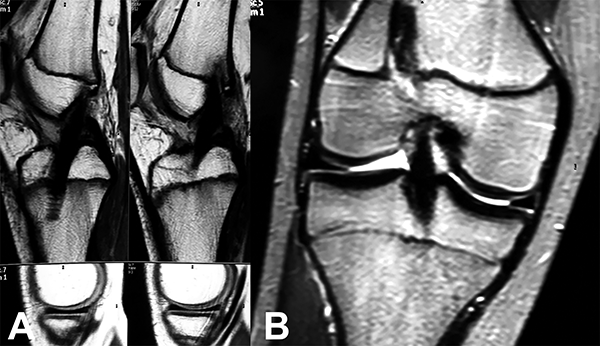

Figura 2: RM de rodilla. Ruptura completa del LCA.

Se le solicitó Rx y RM de rodilla al año y dos años postquirúrgicos (fig. 7).

Figura 7: RM de rodilla a un año de evolución.